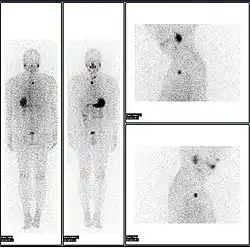

- 2D: Сцинтиграфия (от лат. «знать») — это использование внутренних радионуклидов для создания двухмерных изображений.

Сканирование костей всего тела с помощью ядерной медицины. Сканирование костей всего тела в ядерной медицине обычно используется для оценки различных патологий, связанных с костями, таких как боли в костях, стрессовые переломы, доброкачественные поражения костей, инфекции костей или распространение рака на кость.

Сканирование перфузии миокарда с помощью ядерной медицины с таллием-201 для изображений покоя (нижние ряды) и Tc-Sestamibi для изображений стресса (верхние ряды). Сканирование перфузии миокарда с помощью ядерной медицины играет ключевую роль в неинвазивной оценке ишемической болезни сердца. Исследование не только идентифицирует пациентов с ишемической болезнью сердца; он также предоставляет общую прогностическую информацию или общий риск неблагоприятных сердечных событий для пациента.

Сканирование паращитовидной железы с помощью ядерной медицины демонстрирует аденому паращитовидной железы, прилегающую к левому нижнему полюсу щитовидной железы. Вышеупомянутое исследование было выполнено с одновременной визуализацией технеция-сестамиби (1-я колонка) и йодом-123 (2-я колонка) и методом вычитания (3-я колонка).

Нормальное сканирование гепатобилиарной системы (сканирование HIDA). Сканирование гепатобилиарной системы ядерной медицины клинически полезно для выявления заболеваний желчного пузыря.

Нормальная лёгочная вентиляция и перфузия (V/Q). V/Q-сканирование в ядерной медицине полезно при оценке лёгочной эмболии.

Сканирование щитовидной железы с йодом-123 для оценки гипертиреоза.